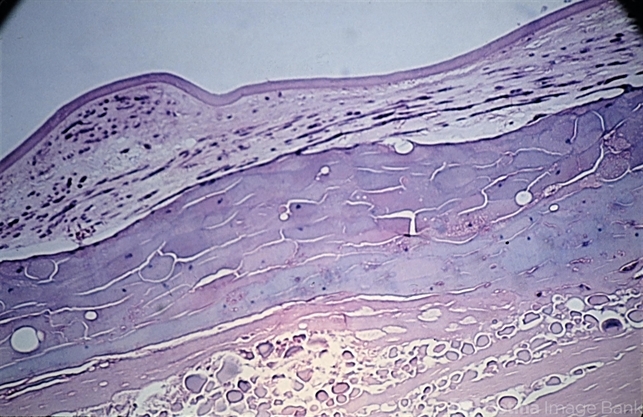

- anterior subcapsular polar cataract, Morgagni's cataract

- Anterior subcapsular cataract associated with morgagnian degeneration of the underlying cortex ( x 40). (Scheie Eye Institute, No. 4076.)